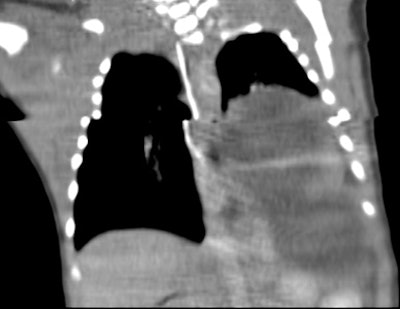

Unsuspected congenital diaphragmatic hernia: The newborn shown below presented with respiratory difficulty, but did not have a scaphoid abdomen. The frontal CXR demonstrated and abnormal lucency and curvilinear density in the left base. A lateral view revealed findings concerning for a diaphragmatic hernia. This was confirmed on CT imaging- note that a portion of the stomach and the spleen have herniated through the defect. |